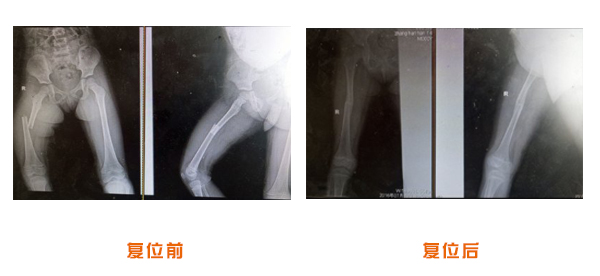

肥城市安駕莊梁氏骨科醫院是一所以梁氏手法正骨配合膏藥為特色的現代化專科醫院。

梁氏骨科術始創于清雍正年間,歷經八代,至今已有三百年歷史。據1929年泰安縣志載“梁瑞圖先生,字增生,號蓮峰,安駕莊人,精岐黃并發明接骨,凡跌打車凡跌打車軋皮不破而碎骨者......【詳細】 |